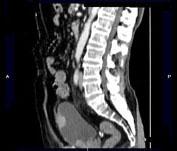

问题 男,73岁,无痛性全程血尿2个月余,CT检查如图所示,下列说法正确的是 ( )

选项 A、考虑为右侧输尿管中下段癌合并膀胱癌 B、考虑为右侧输尿管及膀胱结核 C、膀胱内可见宽基底的软组织肿块影 D、右肾及输尿管上段扩张积水 E、右输尿管中下段可见沿输尿管走行的长约10.6cm,不规则的软组织肿块影

答案 ACDE